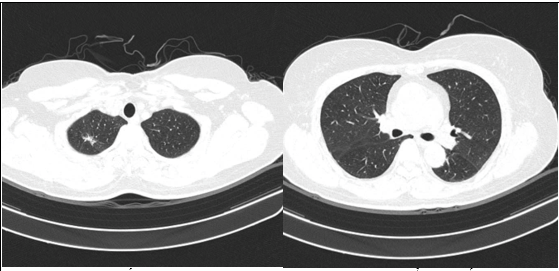

- Cắt lớp vi tính lồng ngực: đám xẹp đông đặc đỉnh phổi phải kích thước 11mm; nhu mô phổi rải rác nốt đặc 5-10mm. Trung thất cân đối có vài hạch 10mm

Hình 6: Hình ảnh cắt lớp vi tính ngực có tiêm: đám xẹp đông đặc đỉnh phổi phải kích thước 11mm (mũi tên xanh nước biển)

Hình 7: Hình ảnh cắt lớp vi tính ngực có tiêm: Trung thất cân đối có vài hạch 10mm (mũi tên vàng). Hạch trung thất giảm kích thước rất nhiều chỉ sau 03 chu kỳ.

- Cắt lớp vi tính lồng ngực: Đám xẹp vùng đỉnh phổi phải, nốt đặc nhỏ kích thước 2-3mm. Không thấy hạch to hay khối trong trung thất

Hình 10: Hình ảnh cắt lớp vi tính ngực có tiêm: Đám xẹp vùng đỉnh phổi phải, nốt đặc nhỏ kích thước 2-3mm

Hình 11: Hình ảnh cắt lớp vi tính ngực có tiêm: Không thấy hạch to hay khối trong trung thất

Nhận xét: Chỉ sau 03 chu kỳ Pemetrexed – Carboplatin – Pembrolizumab, hình ảnh chụp cắt lớp vi tính cho thấy tổn thương phổi nguyên phát và các hạch giảm kích thước đáng kể. Đáp ứng điều trị được đánh giá là đáp ứng một phần theo tiêu chuẩn RECIST 1.1. Sau 9 chu Pemetrexed – Pembrolizumab, bệnh nhân tiếp tục ghi nhận cải thiện rõ rệt các triệu chứng lâm sàng, thể trạng ổn định, không xuất hiện tác dụng không mong muốn nghiêm trọng.Đánh giá trên hình ảnh chụp cắt lớp vi tính cho thấy tổn thương phổi nguyên phát tiếp tục giảm kích thước không ngấm thuốc chỉ còn là đám xơ xẹp vùng đỉnh phổi phải, các hạch trung thất và ngoại vi thu nhỏ rõ rệt, không phát hiện được trên phim chụp và không ghi nhận tổn thương di căn mới.